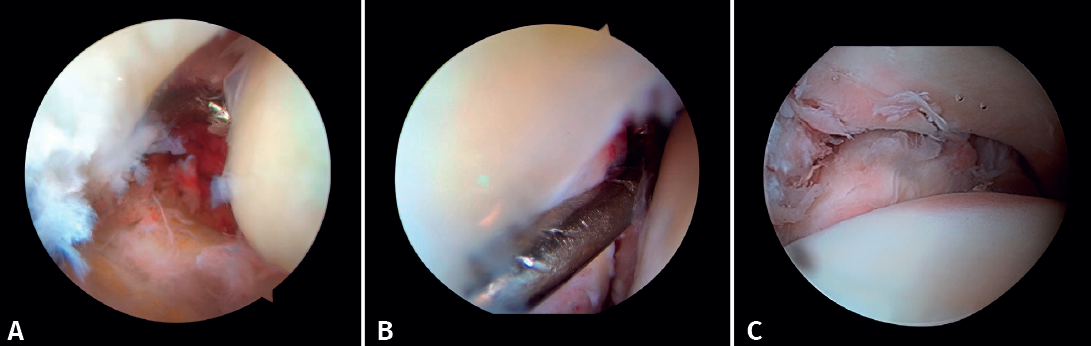

2. Open reduction and internal fixation of the lateral and/or medial malleolus

Arthroscopy assists ORIF in evaluating the congruence of the joint surface. It is especially useful for reduction of the medial malleolus. The malreduction rate in medial malleolus fractures is 22.2-32.6%(15,16). Initial arthroscopy allows us to determine whether tibial malleolus reduction can be performed in an open or closed manner. In cases with significant displacement, open synthesis is chosen, always maintaining arthroscopic control during the procedure to ensure precise reduction and avoid rotation of the distal fragment (Figure 4).

Patients at greatest risk of malreduction are those over 60 years of age, due to decreased bone quality and more complex fractures(17). Patients with open fractures and fracture dislocations have a 2.15 to 2.7 times higher risk, respectively, due to increased soft tissue damage and fracture complexity. Vertical fractures and with interposed soft tissues make it difficult to achieve anatomical reduction(15,16).

If the deltoid ligament injury involves only the anterior part, arthroscopic reinsertion can be made using resorbable implants. If deltoid ligament disinsertion is complete, open reinsertion is preferred, because of the difficulty of placing the implants in the posterior malleolus and the risk of neurovascular injury (Figure 5).